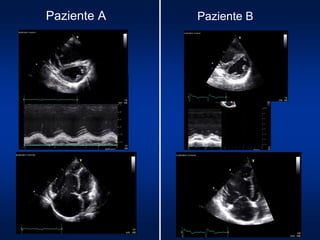

Paziente A Paziente B

donna, HIV+, anni 43 donna, IP idiopatica, anni 28

Classe WHO III Classe WHO II

6MWT: 470 mt

Fc 75 bpm; SO2 98%

Fc 106 bpm; SO2 97%

6MWT: 280 mt

Fc 90 bpm; SO2 95%

Fc 118 bpm; SO2 92%

BNP 890 pg/ml BNP 155 pg/ml

Cateterismo cardiaco destro

PAPm 40 mmHg

PW 9 mmHg

GTP 31 mmHg

CI 2.01 l/min/m2

PAD 13 mmHg

PVR 11 UW

PW 10 mmHg

GTP 30 mmHg

CI 2.45 l/min/m2

PAD 5 mmHg

PVR 6 UW